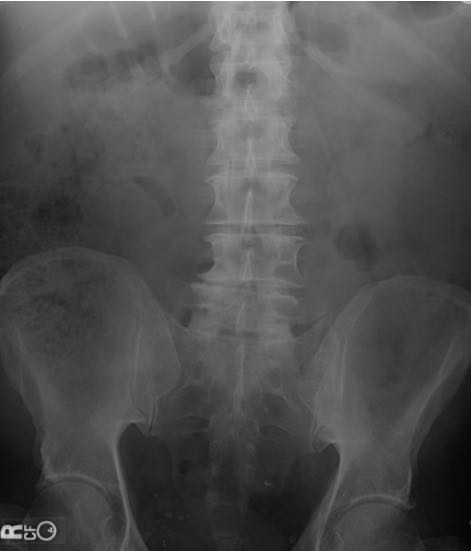

体格检查,体温升高到39.4℃,血压130/76mmHg,脉搏110次/分,呼吸20次/分,非急性窘迫,但有轻微的出汗。口咽清晰,有粘膜干燥。肺部听诊清音,心率正常,无杂音。 腹部检查显示左下象限中度压痛,有腹壁紧张。无反跳痛。无脊肋角压痛,未见腹股沟疝,生殖器检查结果均正常。直肠指诊,左侧直肠穹隆柔软,愈创木脂阴性。其余体检结果无异常。 血清实验室检测仅白细胞升高,为16×103/µL,其中中性粒细胞显著,尿检无异常。标准拍摄腹部平片,未见任何明显异常。后进行腹部和骨盆的CT